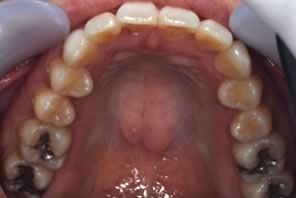

初診時

初診の状態です。 歯列不正の影響で咬み合せが悪く、顎関節に痛みが出ているような症例です。

顎関節の症状を改善するには、咬み合せを治す必要があります。